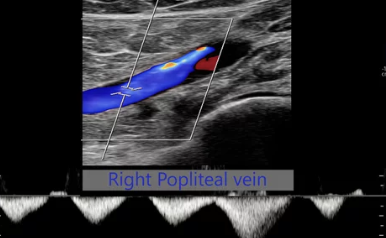

하지정맥 초음파 검사는 하지정맥류 진단의 가장 기본적이고 중요한 검사입니다. 혈관 초음파를 통해 다리 정맥의 상태, 혈액 역류 여부, 혈전 유무 등을 확인하여 정확한 진단을 내릴 수 있습니다.

- 검사 진행: 침대에 누워 검사 부위에 젤을 바른 후, 초음파 기기를 이용하여 다리 정맥을 관찰합니다. 검사 시간은 약 30분~1시간 정도 소요됩니다.